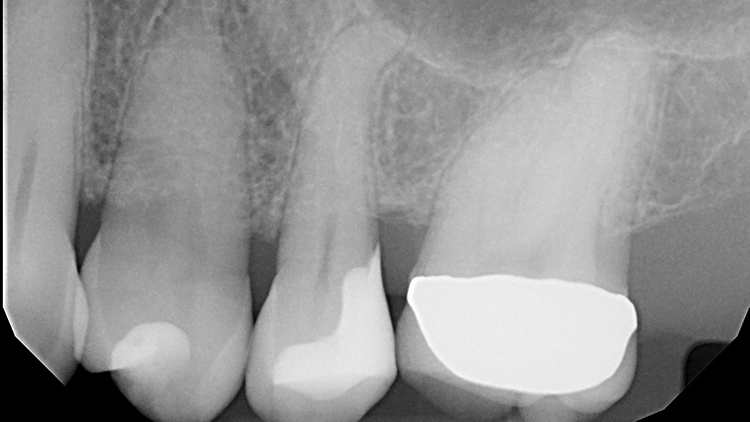

Zur Illustration der Indikation „Inlayaustausch“ dienen die folgenden 3 Fallbeispiele: Die beiden ersten zeigen die Versorgung des Zahnes 45, wobei es im 1. Fall um den Ersatz eines Goldinlays und im 2. Fall eines Keramikinlays geht. Beide Kavitäten wurden mit der neuen Universalfarbe Venus Diamond ONE (Kulzer, Hanau) versorgt.

Fall 1: Austausch eines Goldinlays an Zahn 45

Da aufgrund der Randdefekte eine Austauschindikation bestand, wurden das Inlay sowie minimale Restkaries entfernt und die Ränder nachpräpariert. Bei einer direkten Komposit-Neuversorgung können im Gegensatz zu einer Neuversorgung mit einem Keramikinlay spitz auslaufende Ränder in Form des alten Federrandes belassen werden, da das Restaurationsmaterial diese Bereiche ausfließen und somit randdicht versorgen kann.

Die Patientin bat damals um einen Austausch des Goldinlays, da ihr keine Möglichkeiten einer Nacharbeitung am Inlayrand angeboten werden konnten. Die Inlayversorgung zeigte sich sehr weit in den Approximalraum ausgedehnt (Abb. 11 und 12), was nach Aussage der Patientin an der damaligen Indikation eines Lückenschlusses zwischen den Zähnen 25 und 26 lag.